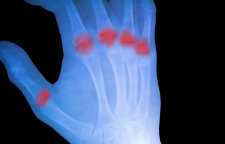

شانه ی یخ زده یا Frozen Shoulder یک بیماری نسبتا شایعی است که کپسول مفصل شانه را درگیر می کند اما تخریب غضروف مفصلی و استخوان را به همراه ندارد. به دنبال آن درد و خشکی و محدودیت حرکت ایجاد می شود. میزان شیوع این بیماری بطور دقیق گزارش نشده است اما گفته می شود که حدود 2 تا 5 درصد جمعیت را درگیر می کند. این بیماری بیشتر در خانم ها و بیشتر در سنین 40 تا 60 سالگی بروز می کند.

التهاب مفصل شانه یخ زده

در شانه ی یخ زده، کپسول مفصلی شانه ملتهب می شود و باند های ضخیم شده ای در بافت کپسول ایجاد می شود که موجب ضخیم شدن و سفت شدن آن و در نتیجه محدودیت فضای مفصلی می شوند. علامت شاخص این بیماری درد شدید و ناتوانی در حرکت دادن شانه، چه با استفاده از کمک و چه بدون آن است.